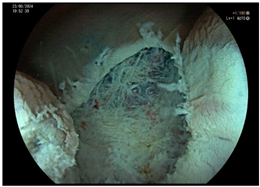

| Endoscopic mucosal resection (EMR) involves injection of a solution into the submucosal space in order to separate the mucosal lesion from the underlying muscularis propria. The lesion can then be resected by snare electrosurgery. The submucosal cushion theoretically reduces the risk of thermal or mechanical injury of the underlying muscularis propria [81]. | ![]() |

| Endoscopic submucosal dissection (ESD) is characterized by three steps: fluid injection into the submucosa in order to swell the lesion from the muscle layer and circumferential cutting of the mucosa surrounding the lesion, followed by dissection of the submucosal connective tissue beneath the lesion (standard technique). The major advantages of this technique in comparison with polypectomy or EMR include control of the resected size and shape, possible en bloc resection even in a large lesion and also resectability of the lesions in case of submucosal fibrosis. Disadvantages include the time-consuming procedure associated with a higher risk of complications (mainly bleeding and perforation) when compared with EMR [83]. | ![]() |